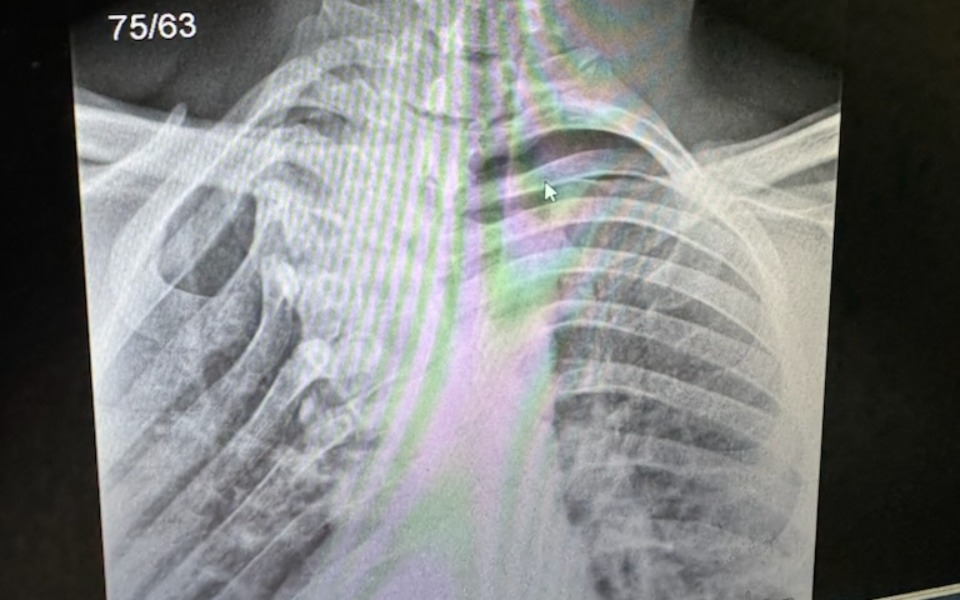

Pieniądze potrzebne są na operacje skręconego kręgosłupa, niestety są tylko dwie kliniki w Polsce, które zajmują się takimi operacjami ale niestety na NFZ terminy są strasznie długie i można czekać bardzo długo a to poważne schorzenie dlatego bardzo proszę o pomoc by móc dać synowi szanse na normalne życie.Tylko prywatna operacja szybko pozwoli w części naprawic kręgosłup bo niestety całkowicie nie da się wyprostować kręgosłupa .Bardzo proszę o pomoc ,wierzę że są dobrzy ludzie i każda złotówka jest darem.Bede dozgonnie wdzięczna za każdą pomoc